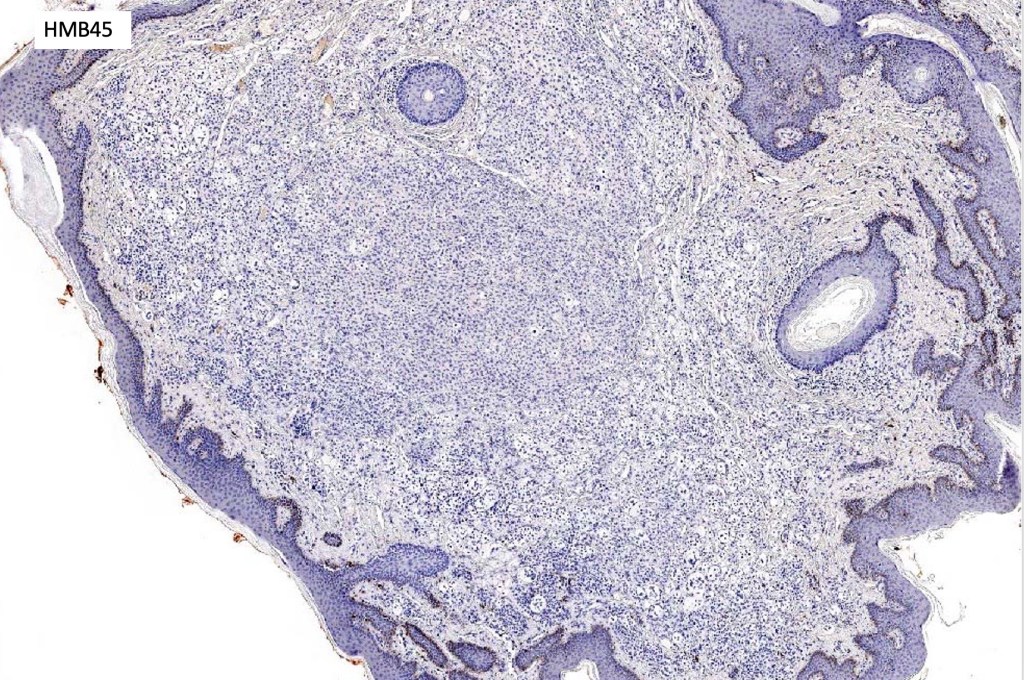

. In some balloon cell nevi, the microvesicles may result in nuclear scalloping reminiscent of a sebaceous tumor. In cases where there is real doubt, immunohistochemistry (S100), SOX10) will resolve the problem.